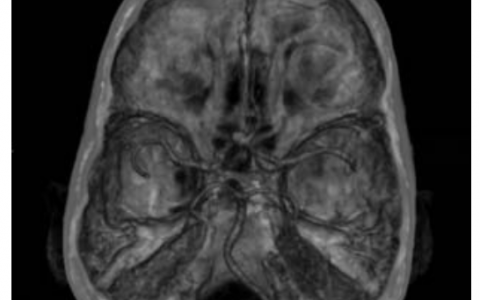

A 68-year-old woman with type 2 diabetes mellitus and a 30-pound weight loss over the past two months presents to the physician with a history of nausea and bloating. Symptoms are most prominent following a meal. An outpatient gastric emptying study shows esophageal dysmotility. The best treatment option for this patient is which of the following?

一名68岁女性2型糖尿病患者因恶心和腹胀病史就诊,过去两个月体重减轻了30磅。饭后症状最明显。门诊胃排空检查显示食管运动障碍。该患者的最佳治疗方案是以下哪一种?

该患者表现为胃轻瘫,尤其是继发于糖尿病的食管运动障碍。食管动力障碍的其他原因包括糖尿病性胃轻瘫、恰加斯病、狼疮和其他胶原血管疾病。初始治疗包括促动力药,甲氧氯普胺是一线治疗。

正确答案:B